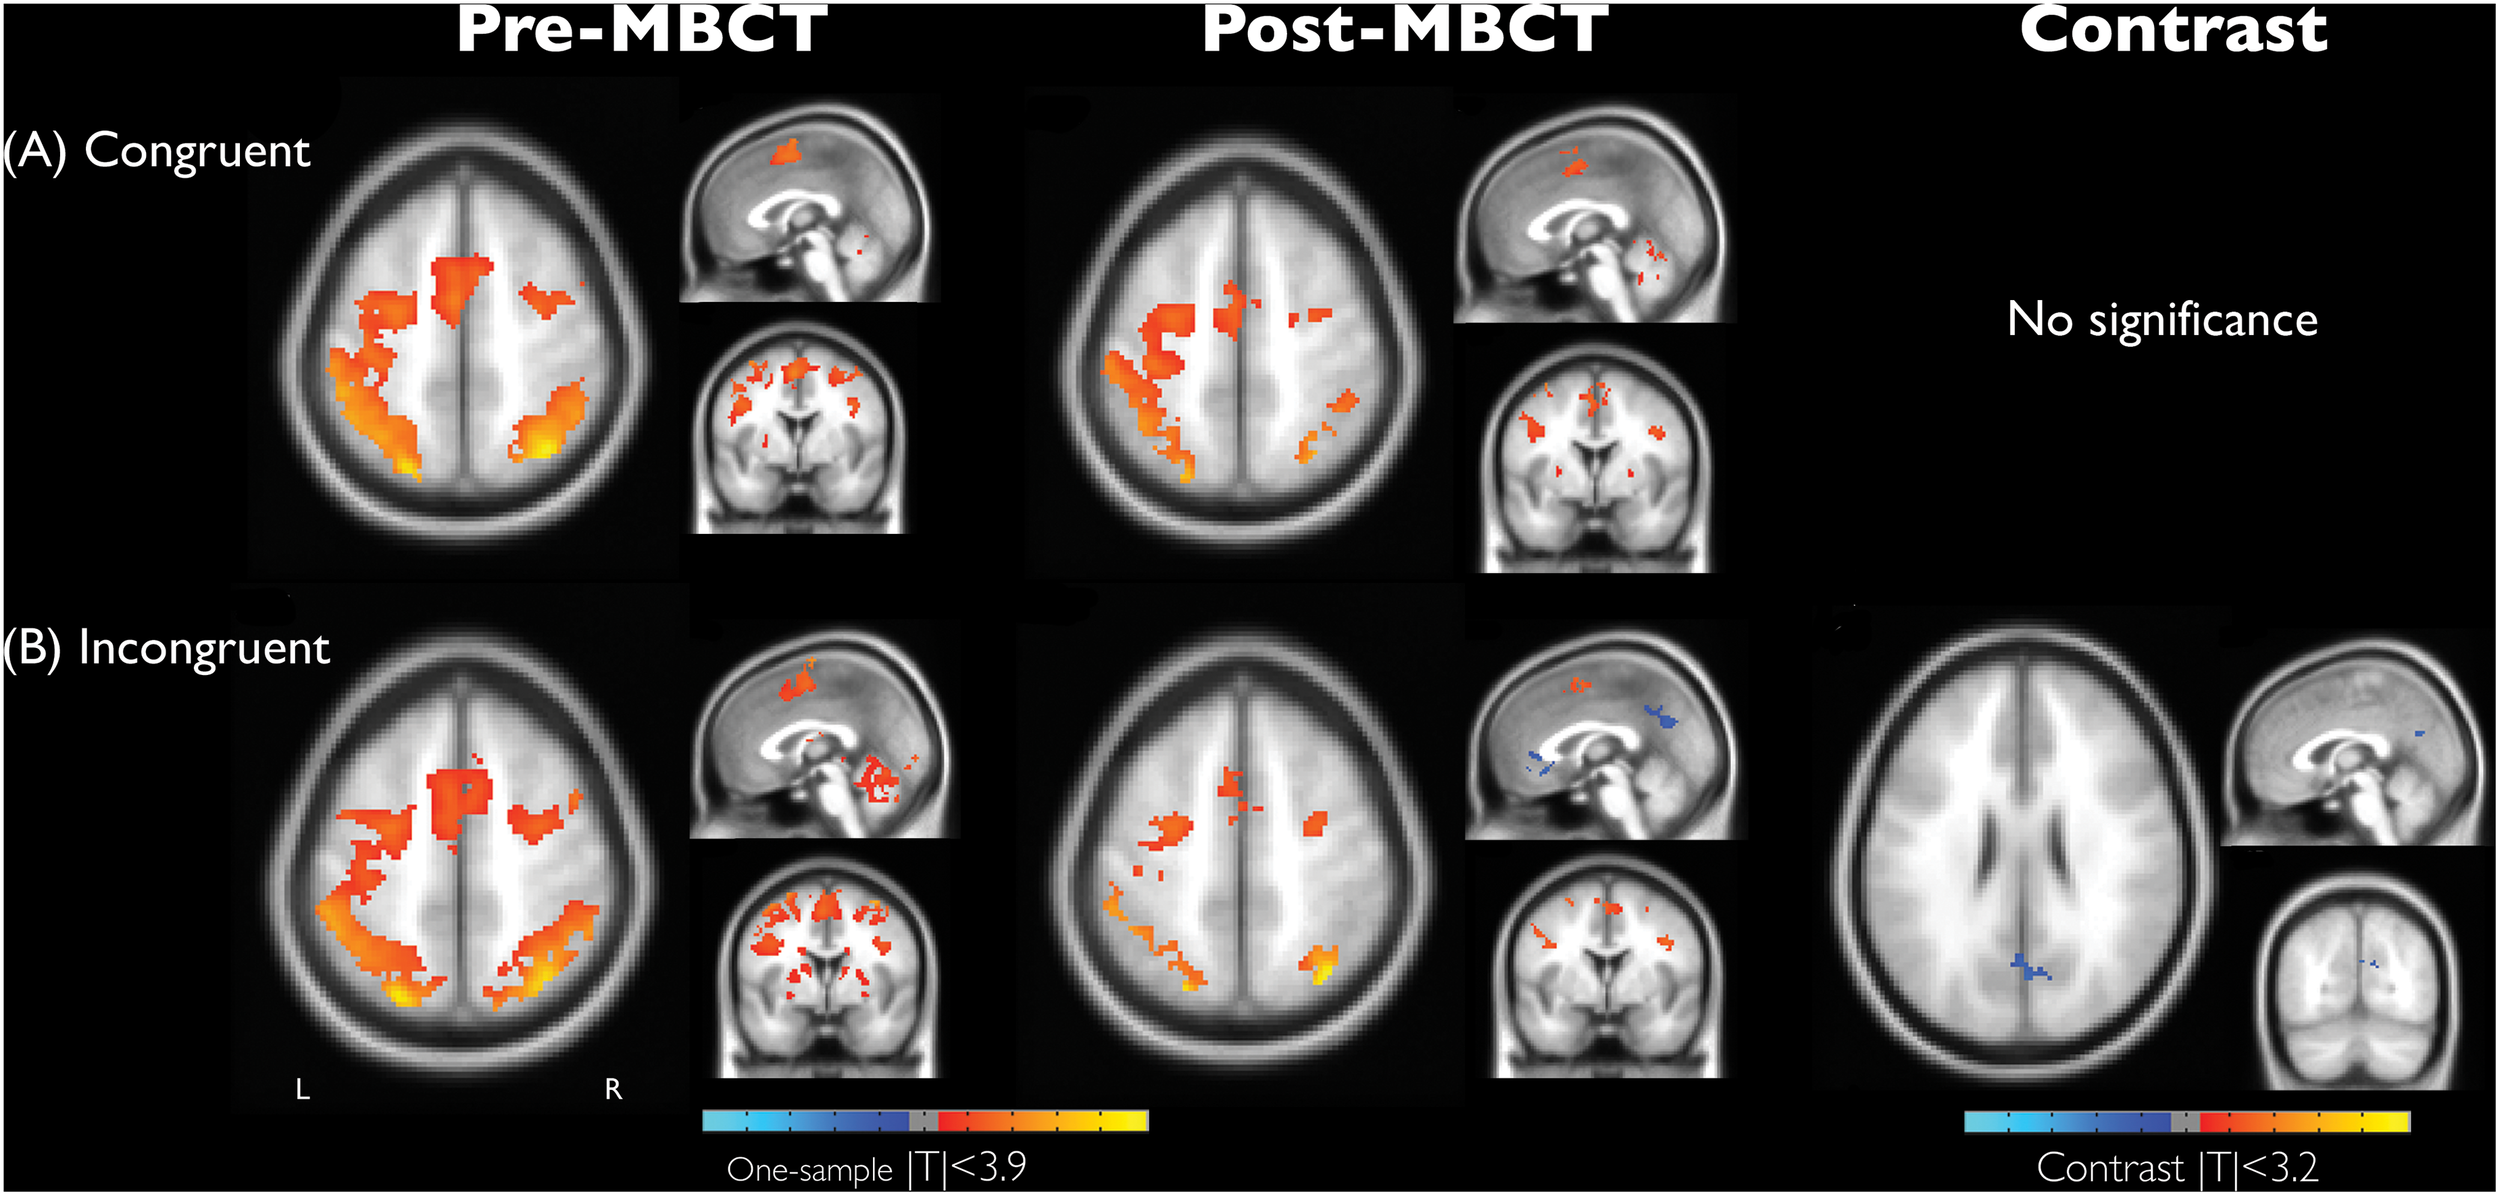

Figure 1 demonstrates the significant recruitment of the dorsal attention network (DAN) in a single session of performing the numerical Stroop task, and the detailed information of brain regions were shown in Tables 3–5. The DAN activation level was generally reduced after MBCT while preserving the accuracy, but the results of incongruent trials, involving in the higher cognitive-load of inhibition, disclosed significant deactivation in both anterior cingulate cortex (ACC) and posterior cingulate cortex (PCC). Similar to the RT results, the congruent trials did not present MBCT effects in brain recruitments, whereas the brain recruitment to incongruent trials after MBCT only showed significant reduction in right PCC/precuneus under AlphaSim p < 0.05. The interaction effect of fMRI results (intervention × condition) showed single negative activation located at PCC, similar as the incongruency outcome. We further evaluated the associations between the neuropsychological assessment and the brain regional activity (PCC and hypothetical thalamus) involved in the incongruent condition of the numerical Stroop task. Figure 2 shows significant correlations (a) between TRIG and PCC; (b) between Anxiety and PCC; and (c) TRIG and thalamus, Spearman’s ρ > 0.33, p < 0.05. Figure 2 demonstrates that less grief and anxiety were associated with reduced brain activations of PCC or thalamus involved in the numerical Stroop task.

FIGURE 1

Brain activation maps associated with condition effect of (A) congruency and (B) incongruency and its difference and the intervention effect (before and after MBCT) in the numerical Stroop task on grief bereavement (AlphaSim corrected p < 0.05). Anatomical images were shown with coordinate location = [0, 0, 52] for one-sample t maps and [–2, –70, 26] for contrast maps. L, the left hemisphere.